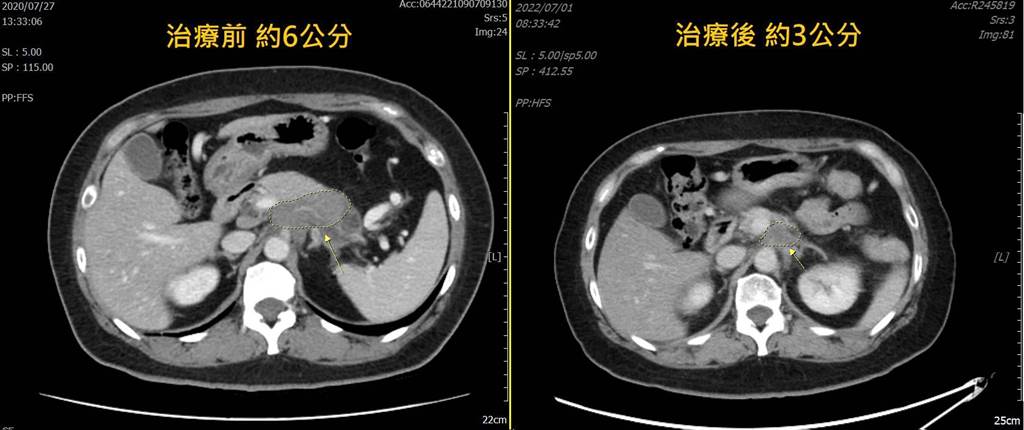

Photo from 中國醫藥大學新竹附設醫院

癌症慢慢回到可控範圍內

醫生續說,患者在3年前的癌症指數原本是高達1587U/ml,而現在已經降至9.1U/ml,腫瘤也從3年前的6公分縮至現在的3公分,可見陳先生的癌症有著非常樂觀與好轉的情況。在陳先生完成放射治療後,精神已明顯有改善,且癌症也慢慢回到可控範圍內。從患病前的80公斤,後來患癌掉至60公斤,現在又慢慢增加至70公斤。